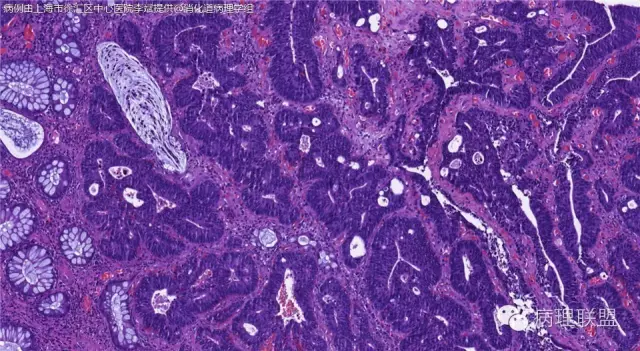

男,72岁,距肛门口30cm息肉。大体:灰白结节1.5*1*0.8cm拟发管状腺瘤并部分区高级别,请各位老师指导!(病例由上海市徐汇区中心医院 李斌 提供,致谢!)

这一例有两种不同看法,按WHO标准,为高级别,按实际工作,要发粘膜内癌。WHO第三版与第四版均提出,侵犯至粘膜下层才能诊断为癌,声称结直肠粘膜内没有淋巴管,发生转移的概率较小,但是粘膜内有血管,肿瘤侵出粘膜腺体基膜以外,就能侵犯血管,照样可以发生血道转移。文献报告与我们的工作实践,发现腺瘤、高级别(没有侵出基膜)的患者,同样有发生血道转移。因此,我们废弃了这一条WHO标准(不是所有的WHO标准都是一定要执行的)。只要异型增生腺体呈毛刺状、迷芽状侵出粘膜腺体基膜,位于粘膜肌层以内,就发粘膜内癌。

@李斌 结肠腺瘤这例我认为已经有黏膜下浸润了,因为有些腺体间的间质已经不是固有膜间质而是促结缔组织增生反应的间质了。但即使有浸润癌,如果息肉完整摘除、癌成分分化好、没有脉管瘤栓、浸润癌距切缘大于1mm(日本标准还要看浸润癌超出黏膜肌深度和肿瘤出芽情况),也不需要进一步治疗。所以,对于这类可能存在争议的病变,特别是息肉已经完整切除的病例,诊断的关注点就应该放在寻找需不需要进一步治疗的证据上了。@邓永键 2010版WHO在腺瘤部分的陈述中已经写出对于有局灶浸润性生长的病例也可以称黏膜内癌,他们在悄悄的让步。